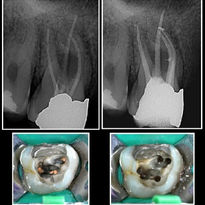

Local anaesthesia is given and the tooth is isolated with a rubber dam (a special hygienic rubber sheet) to prevent contamination of the tooth from saliva and to protect the patient from accidently swallowing any chemicals or foreign objects. An opening is made through the chewing surface of the tooth to gain access to the root canal system. The pulp tissue is painlessly removed with special endodontic files. Root canal lengths are measured with an electronic locator and confirmation takes place by means of an x-ray. The root canal/s are cleaned, disinfected, enlarged and shaped with rotary instruments and chemicals. The root canal/s is filled with a rubber substance called gutta percha that is plasticised with heat to obtain a three dimensional filling of the prepared root canal spaces. The tooth is then restored with a foundation filling and the tooth is ready for the referring dentist to place a crown on the tooth.

This procedure takes place over one or two visits. During the first visit the failed root canal therapy filling is removed. The canal/s is prepared similar to a normal root canal procedure. A medicament is placed in the affected area and completion of the procedure takes place with seven days.